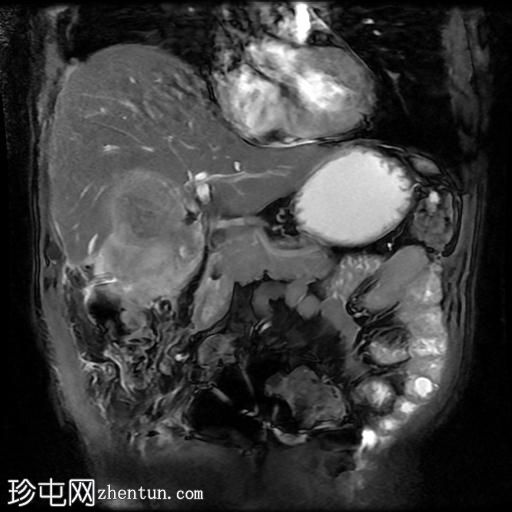

冠状位T2加权像

脂肪抑制像

胆囊切除术后,可见肝总管局部断裂,尤其是在胆囊管开口上方。该断裂伴有胆囊切除部位形成较大的血肿或胆汁瘤。

胆管损伤可能发生在手术过程中,导致胆汁渗漏到周围组织,从而形成血肿或胆汁瘤。这可能出现明显的临床症状,并可能需要进一步干预,具体取决于病情的严重程度和患者的临床表现。